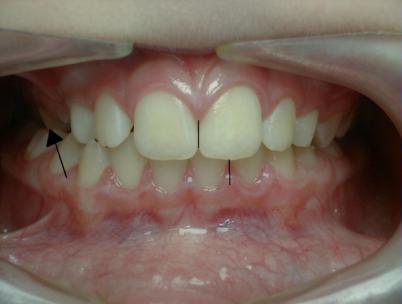

Inversé articulé précoce

Inversé unilatéral à droite